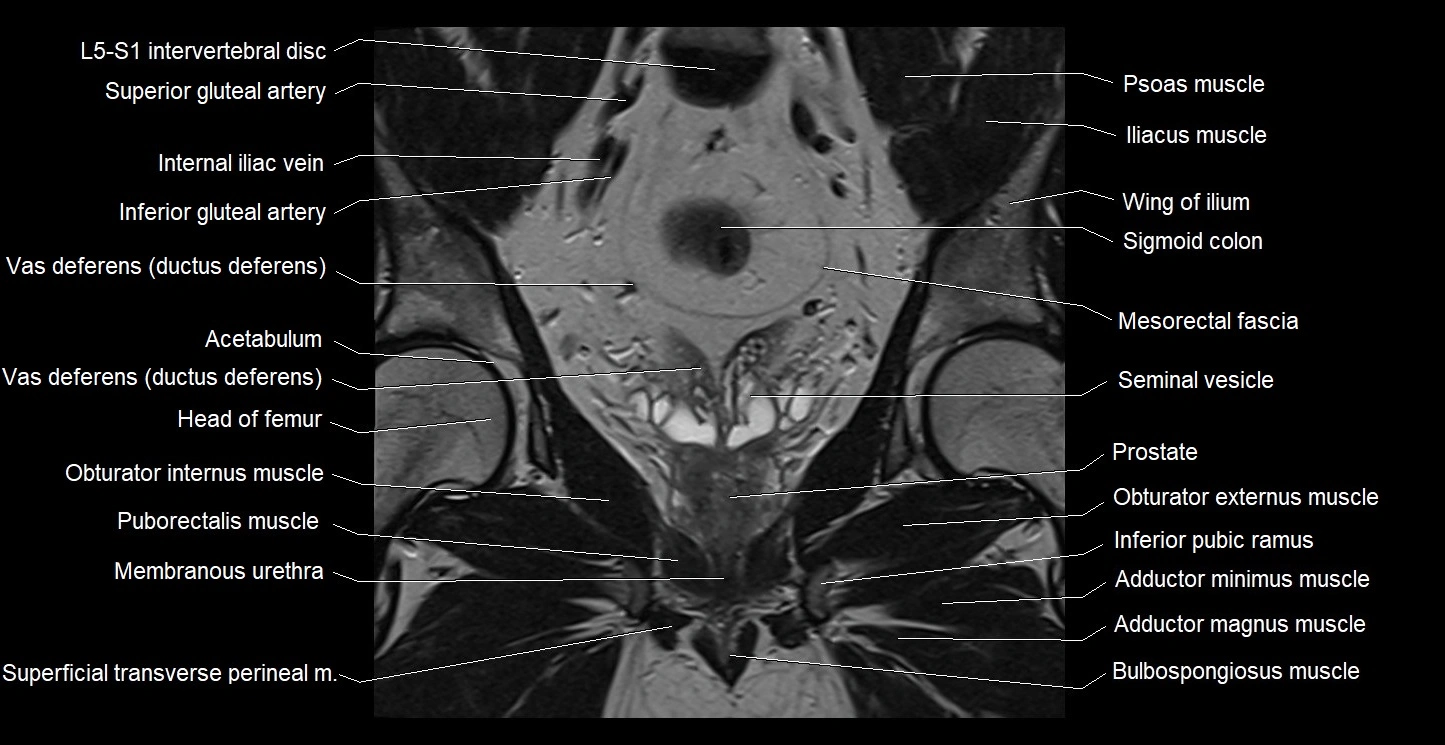

- Acetabulum

- Adductor brevis muscle

- Adductor longus muscle

- Adductor magnus muscle

- Adductor minimus muscle

- Bulbospongiosus muscle (Male)

- Head of femur

- L5–S1 Intervertebral disc

- Membranous urethra

- Mesorectal fascia

- Obturator externus muscle

- Obturator internus muscle

- Pectineus muscle

- Peripheral zone of prostate

- Puborectalis muscle

- Seminal vesicle

- Sigmoid colon

- Superficial transverse perineal muscle

- Transitional zone of prostate

- Vas deferens